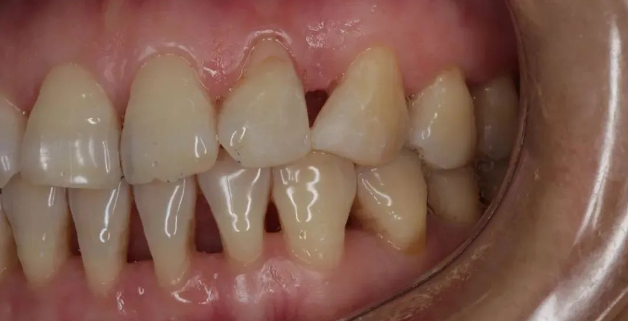

之后,牙齿会出现松动,时不时有脓液流出来。

再后来,牙齿和牙齿之间的缝隙越来越大,而之前松动的牙齿开始摇摇晃晃,有的人还会出现牙痛。这时候吃药止痛,已经无济于事。随着牙周炎的进展,病变越来越深入牙龈深处。

△随着牙周炎的进展,病变越来越深入牙龈深处。